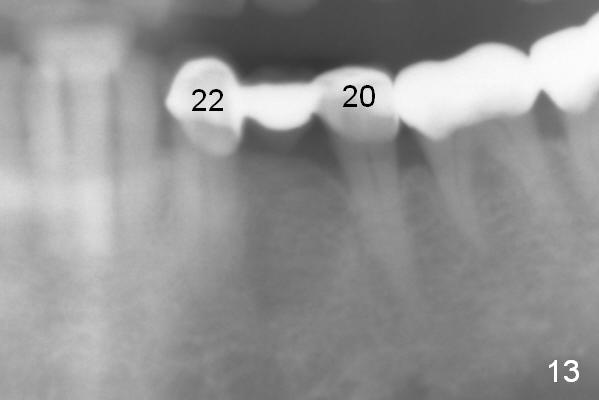

The fistula buccal to #14 remains 1 week postop (Fig.7) and disappears 1 months postop. The fistula does not re-appears 3 months postop with the implants at #13,15 apparently osteointegrated (Fig.8). With relining #13-15 provisional with increased vertical height (Fig.11), the patient has bilateral posterior contact (Fig.9), while the lower incisors do not contact the cinguli of the upper incisors (Fig.10 *). The space between the tooth #12 and the pontic #21 is unfavorable for posterior occlusal stability (Fig.11 *). Porcelain is chipped off the buccal surface of the pontic (Fig.12 *). If the patient does not afford an implant at #21 with redo crowns at #20 and 22 (Fig.13), what else could be done? He will return for #15 implant placement 4 months post socket preservation.